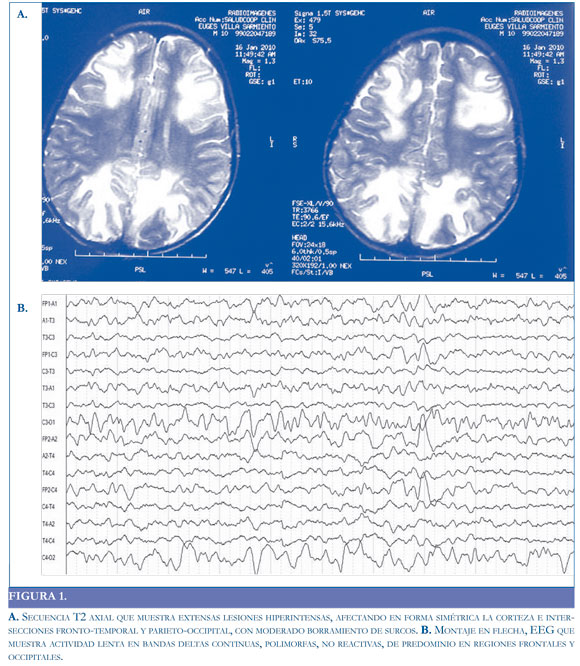

Se realizó RM, que mostró lesiones hiperintensas, afectando en forma simétrica la corteza e intersecciones fronto-temporal y parieto-occipital, con moderado borramiento de surcos; y EEG que con hallazgo sugestivo de disfunción subcortico-cortical difusa y bilateral (Figura 1).

Además de la resonancia, ante un paciente con signos que sugieran encefalopatia o encefalitis, el EEG tiene gran importancia al demostrar la disfunción de la actividad eléctrica cerebral (cortical o subcortical) y su progresión.

Los hallazgos electroencefalográficos en pacientes con encefalitis o encefalopatía no son específicos, los más frecuentes corresponden a lentificación del ritmo de fondo, por lo que el análisis visual del electroencefalograma deber ser ordenado y orientado al estudio de las ondas lentas y debe incluir: frecuencia, morfología, localización (focal o generalizada), reac-

tividad, periodicidad y patrones particulares (17, 18).

Algunos autores sugieren que si el compromiso es cortical (sustancia gris), predomina la actividad delta polimorfa y si el compromiso es subcortical, los patrones arrítmicos son más comunes. Por lo general, la severidad del cuadro clínico se corresponde con las anormalidades registradas en el EEG (19). En el caso presentado, el EEG en la etapa aguda de la enfermedad mostró un ritmo de fondo delta, polimorfo, difuso (bilateral), no reactivo que se fue organizando en la medida en que el paciente fue mejorando clínicamente.